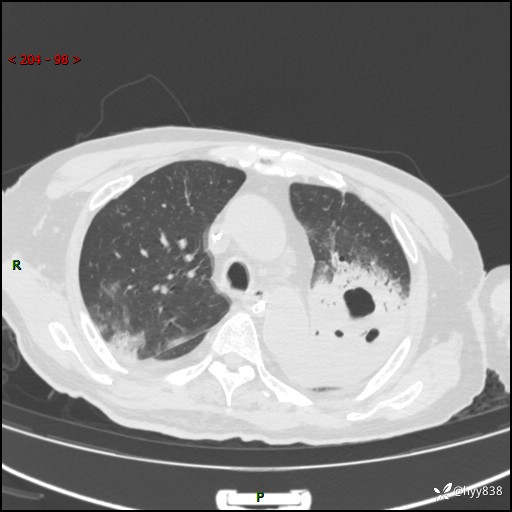

胸部CT平扫(2024.7.24)